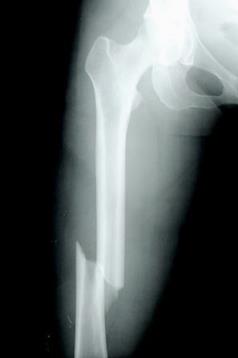

Entonces este producto agrava o acelera la osteoporosis, mal que debilita los huesos, haciéndolos frágiles y más propensos a romperse.

Se desarrolla lentamente durante varios años y, a menudo, solo se diagnostica cuando una pequeña caída o un impacto repentino causa una fractura ósea. Las lesiones más comunes en las personas con osteoporosis son fracturas de muñeca, cadera y espina ósea. Sin embargo, también pueden ocurrir en otros huesos, como en el brazo o la pelvis.